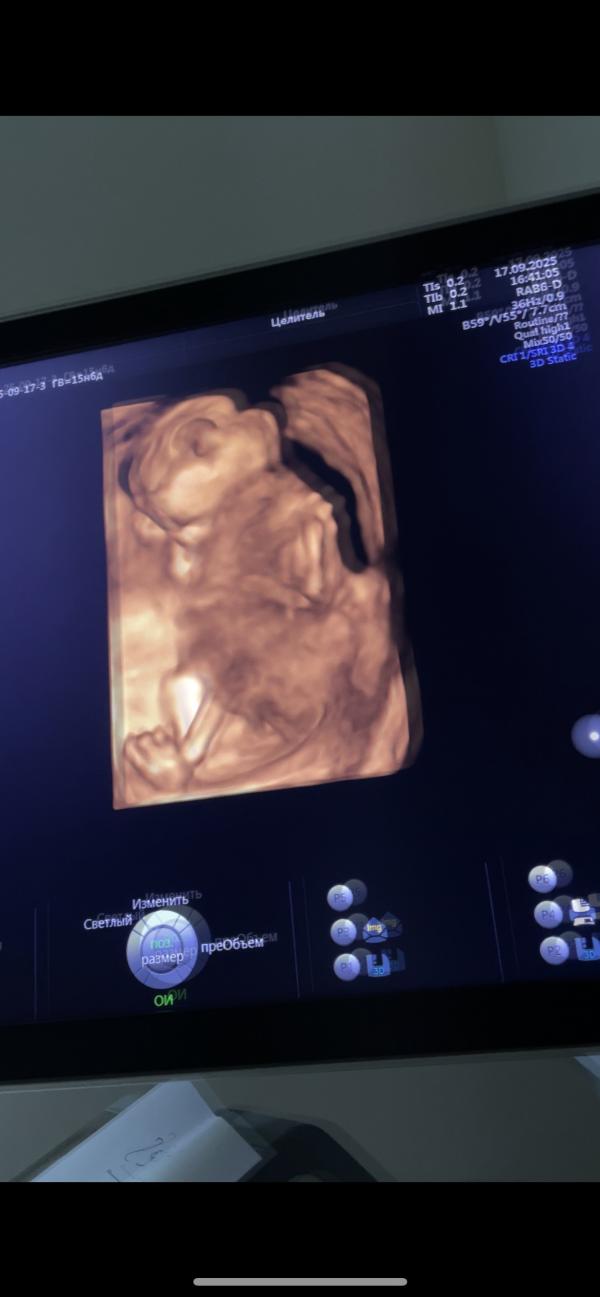

Вторая беременность: эмоции УЗИ и ожидание 2 скрининга

post image 1

на эти пальчики - долмашки🥲😂

сколько я умилялась на узи, такие эмоции испытала вновь…

маленький малыш💖

вес - 160 гр

не на секунду этот малыш не остановился, то ножками то ручками))

из-за тонуса бедный лежит согнув коленки

единственное жду теперь 2 скрининг, чтобы изучили сердце полностью, пока сказали поверхностно все хорошо, присутствуют все 4 камеры)